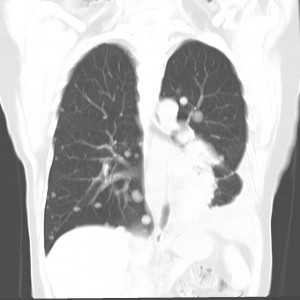

КТ ОГК. Множественные мягкотканные очаги в обоих легких у пациента с первичным раком предстательной железы

Компьютерная томография — один из самых чувствительных и распространенных методов диагностики метастазов в легкие. Это исследование позволяет выявить очаги опухоли меньше 1 мм в диаметре. Более чувствительным и специфичным методом является только ПЭТ/КТ, но он меньше распространен, дороже и сложнее в применении.Для выявления мелких очагов лучше использовать спиральную компьютерную томографию. Чтобы определить метастазы в легкие, контрастное усиление не является обязательным, но может быть полезным для дифференцировки легочных сосудов и лимфоузлов при их вторичном поражении.

КТ-ПРИЗНАКИ МЕТАСТАЗОВ В ЛЕГКИЕ

Метастазы чаще всего представлены узловыми образованиями в легочной ткани вне строгой связи с легочными артериями или венами. Для них характерны следующие КТ-признаки:

Вторичные узлы гематогенного характера чаще всего имеют ровные края, четкие контуры и однородную структуру. Возможны изменения структуры опухоли вследствие кровоизлияния в паренхиму, обызвествлений, некроза центральной части узла, а также рубцов. Края узла могут стать нечеткими, расплывчатыми, если опухоль провоцирует отек легочной паренхимы, либо «лучистыми», если имеет место опухолевый лимфангиит.

КТ: метастазы в легких при раке молочной железы. На изображении справа красной звездочкой отмечен опухолевый узел в молочной железе, красными стрелками - область прорастания опухоли в грудную стенку. Синими звездочками отмечен карциноматозный плеврит — скопление жидкости в плевральной полости. Слева стрелкой отмечен вторичный узел.